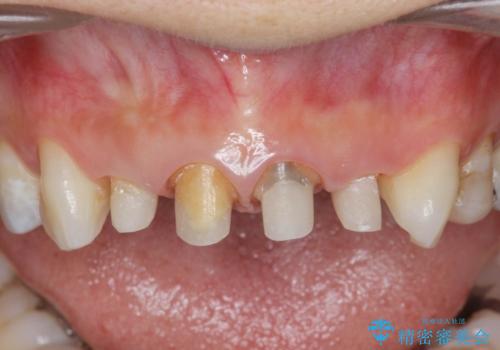

- 「黒ずんで、見栄えの悪い前歯をきれいにしたい。」と、前歯のセラミック治療を希望され来院されました。

全て根管治療のすでになされている歯の変色で、オールセラミッククラウンによる審美性の改善を計画します。

- 52.8万円(ジルコニアクラウン×4・仮歯×4)費用は治療当時の料金となります

自然で美しい前歯の仕上がりとなり、大変満足していただくことができました。